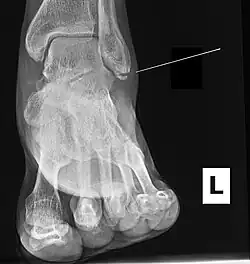

Fracture of the medial malleolus seen on X-ray scan (left ankle)

Common symptoms of a Maisonneuve fracture are pain, swelling, tenderness, and bruising around the ankle joint and inferior (or distal) tibiofibular joint. More specifically, as a pronation-external rotation injury, pain during external rotation of the ankle joint is expected. Additionally, there is a reduced range of motion of the foot and an inability to weight-bear due to ankle pain.[4][7] Pain may also be felt around the medial and lateral aspects of the ankle, and more rarely around the superior (or proximal) tibiofibular joint.[9] Damage to the deltoid ligament or interosseous membrane can cause haemorrhaging around the surrounding tissues, resulting in a localised oedema.[8]

Fracture of the lateral malleolus seen on X-ray scan (left ankle)

Ankle radiographs are used to detect widening of the tibiofibular syndesmosis or medial clear space. The medial clear space is the area between the talus of the ankle and the medial malleolus. Damage to the deltoid ligament and syndesmotic ligaments result in mortise instability, causing the talus to laterally shift and widen the medial clear space.[4][12] A clinical study, conducted in 2006 and published in the Journal of Bone and Joint Surgery, found that the medial clear space size of a normal ankle and an injured ankle measured at 4 millimetres and 5.4 millimetres in length respectively.[11] To confirm diagnosis, full-leg radiographs are used to inspect for fractures of the proximal fibula and widening of the interosseous clear space (or tibiofibular clear space). The interosseous clear space is the area between the medial side of the fibula and lateral side of the tibia. A peer-reviewed study, published in Injury in 2004, found that an interosseous clear space greater than 10 millimetres indicates diastasis of the syndesmotic ligaments.[4]

If necessary, computed tomography (CT) or magnetic resonance imaging (MRI) may also be used to clarify diagnosis. MRI scans can check for interosseous membrane or tibial tubercle damage if high instability of the ankle is diagnosed.[8][11] Arthroscopy may be used to diagnose a syndesmotic lesion but is often not recommended due to operative difficulty.[13] Stress radiographs of the ankle are used to assess the integrity of the deltoid ligament and tibiofibular syndesmosis.[9][13] The size of the medial clear space can also be measured using stress radiography.[11]